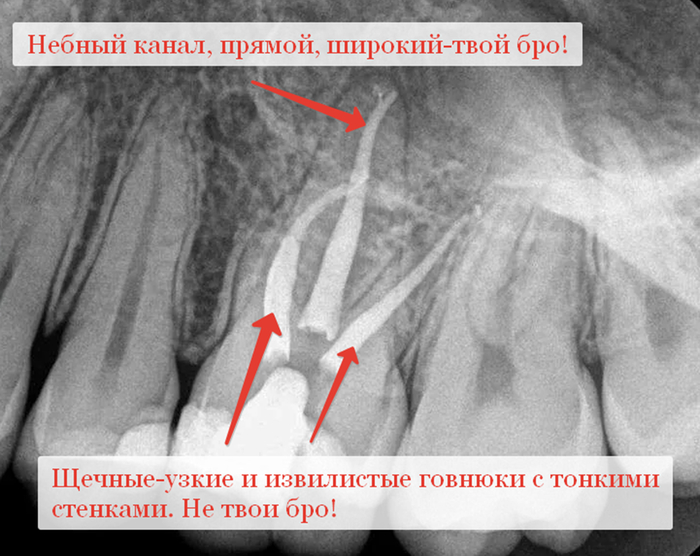

-Анатомия некоторых корневых каналов не всегда позволяет их распломбировать их так. Чтобы не ослабить потом зуб. Например, небный канал у верхних 6 и 7 зубов и задний канал у нижних, как правило, прямые, широкие, с толстыми стенками. Их легко найти, легко расширить до нужного размера, чуть ли не до самой верхушки. Если говорить про щечные и передние каналы, то они, как правило, узкие, кривые, с тонкими стенками, их устья находятся где-то в заднице. Также их корни имеют различные инвагинации и поднутрения, отчего даже просто их пролечить или запломбировать становиться проблемой, не то, что засунуть туда штифт и дать на него нагрузку.